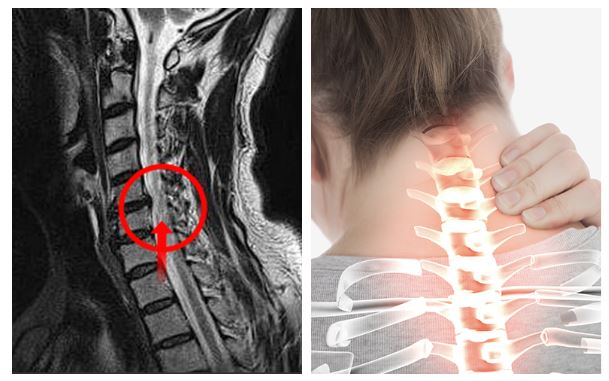

추간판의 수핵이 빠지거나 퇴행성 경추증 및 경추관협착증 등으로 척수가 압박되면 대다수 팔에 힘이 빠지는 것을 느끼게 돼요. 척수가 눌리는 정도이기 때문에 한쪽 팔만 마비될 수 있고요. 하지마는 양팔의 감각이 둔해지고 눈을 감고도 어지럽기 때문에 이러한 목 디스크 증상이 나타나면 무척 위험한 상태가 되기 때문에 빨리 치료가 필요해요.